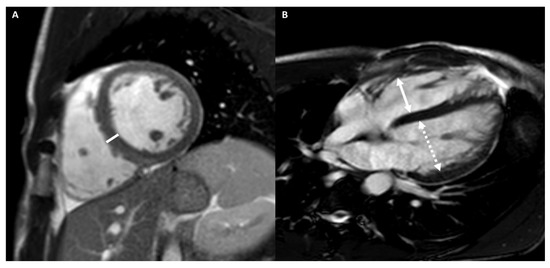

4.2.3. Cardiac Imaging: AH vs. Left Ventricular Non-Compaction

4.2.4. Cardiac Imaging: AH vs. Arrhythmogenic Cardiomyopathy

- Negri, F.; De Luca, A.; Fabris, E.; Korcova, R.; Cernetti, C.; Grigoratos, C.; Aquaro, G.D.; Nucifora, G.; Camici, P.G.; Sinagra, G. Left ventricular noncompaction, morphological, and clinical features for an integrated diagnosis. Heart Fail. Rev. 2019, 24, 315–323. [Google Scholar] [CrossRef] [PubMed]